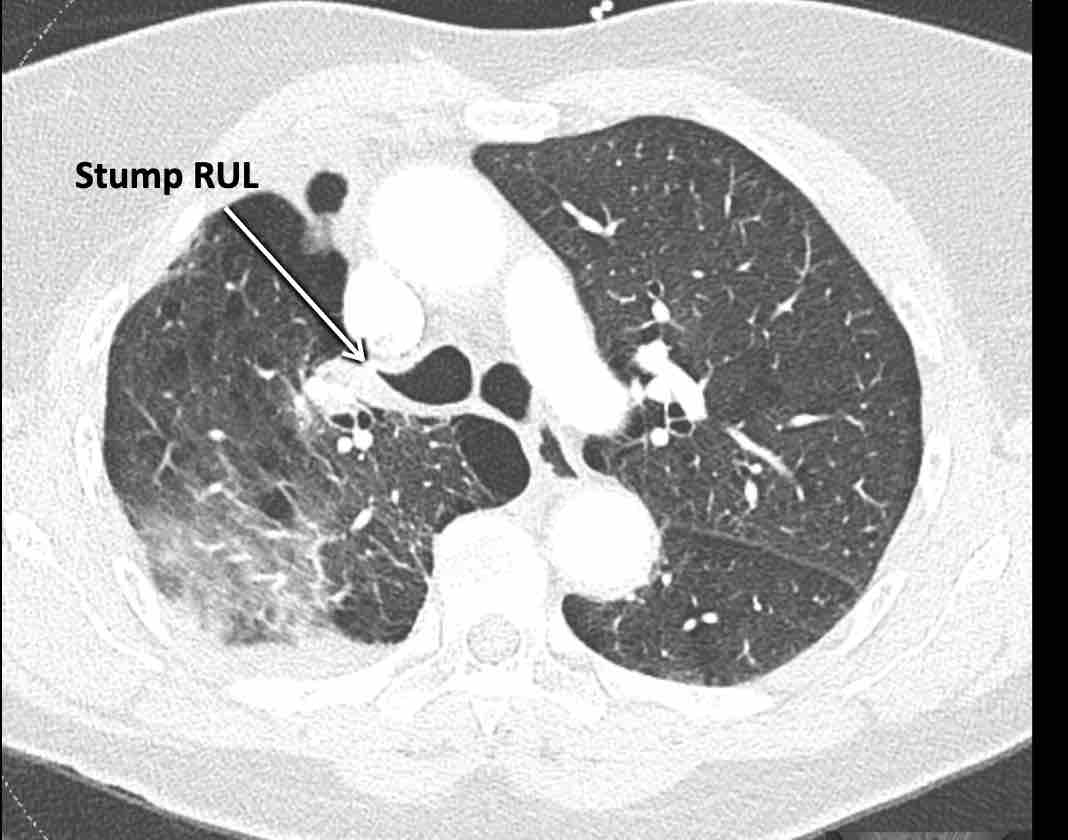

Các hình ảnh này của một bệnh nhân nữ 65 tuổi sau khi đã cắt thùy trên phổi phải trước đó.

Trước tiên, hãy cuộn qua các hình ảnh.

Hình ảnh

Theo dõi lần lượt các phế quản giúp xác định mỏm cắt thùy trên phổi phải (RUL), phế quản thùy giữa bị tắc nghẽn và các phế quản thùy dưới còn thông.

Điều này xác định mô phổi bị di lệch xuống dưới chính là thùy giữa phổi phải (RML), thấy rõ nhất trên mặt phẳng đứng dọc.

Thùy giữa phổi phải bị phù nề và không còn được tưới máu.

Ngoài ra còn thấy hình ảnh ứ máu và xẹp phổi ở các phân thùy đáy của thùy dưới phổi phải (RLL), hiện nằm phía trên thùy giữa phổi phải đã bị nhồi máu.